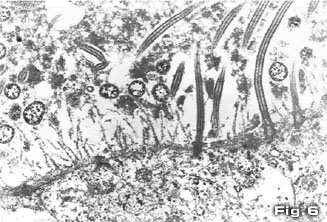

La adhesión del micoplasma a los cilios de las células

epiteliales provoca, por un lado, su pérdida, (Fig.

5) comprometiendo el mecanismo defensa y por otra,

un efecto citopático sobre la célula lo que

se atribuye, no sólo a la capacidad de adhesión,

sino también a una competencia metabólica entre

el agente patógeno y la célula epitelial. La

muerte celular consiguiente y su descamación provocan,

como respuesta, una hiperplasia epitelial que intenta reparar

la pérdida de las células (Fig.

6) (Kobisch y Friis, 1996).